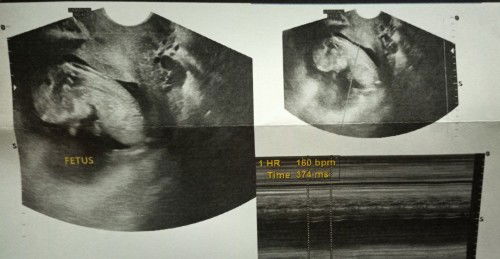

Sharing my US @ 12 weeks 0 days baby and my experience in 1st trimester.

This was my first ultrasound via TVS. If base on my LMP 13 weeks and 3 days but base on the ultrasound and length of my baby 12 weeks and 0 days with 160bmp heartbeat. I was 2 months delayed before I got my serum test with positive result of pregnancy and after 2 days I test again through urine test (di po kasi ako makapaniwala dahil medyo may katagalan ding hinintay). Before I knew I was pregnant, in those 2 months I experienced nausea twice early in the morning and thought it was normal kasi acidic din ako. Palagi na rin akong inaantok, gutom at tinatamad kumilos. I have also breast tenderness within those months at plan ko talaga na i.observe muna yung sarili ko at magpa delay ng 2 months para sure na positive talaga. Regular naman ang period ko kaso nung nagbalak na kaming mag conceive nadedelay na ko ng sobra 1 month and kapag mag.PT naman ako palaging negative and pagka next day meron na kong period kaya nawalan din ako ng pag-asa. After namin nalaman na positive talaga, we made an appointment sa OB para my advice at maresetahan ng vitamins and dun na lumabas yung mga weird na symptoms ko in pregnancy. Wala naman akong morning sickness aside sa nasusuka at sensitive sa pang amoy and nawalan na ko ng gana kumain kahit pa gustong gusto ko dahil parang ang bilis kong mabusog. Nagkaron din ako ng contact dermatitis sa mukha at binti and dandruff na parang natutubig na yung scalp ko sa sobrang kati so another check up naman sa derma. After naman akong naresetahan ng soap and cream nawala na rin naman. Another thing is sa 1st ultrasound ko nakitaan din ng endocervical polyp pero malayo layo naman sa cervix ko and according to my OB di na need mag pap smear at my possibility naman na mawala kapag ma deliver ko na si baby, yun nga lang at more on bed rest kasi my times din na nagkaron ako ng brown discharge and possible na sa polyp siya as long as wala namang contraction and inum kagad ng pampakapit. I'm currently 17 weeks 4 days and waiting for my next check up and ultrasound for my baby's condition and gender. #1stimemom #pregnancy #firstbaby #Share2langpo